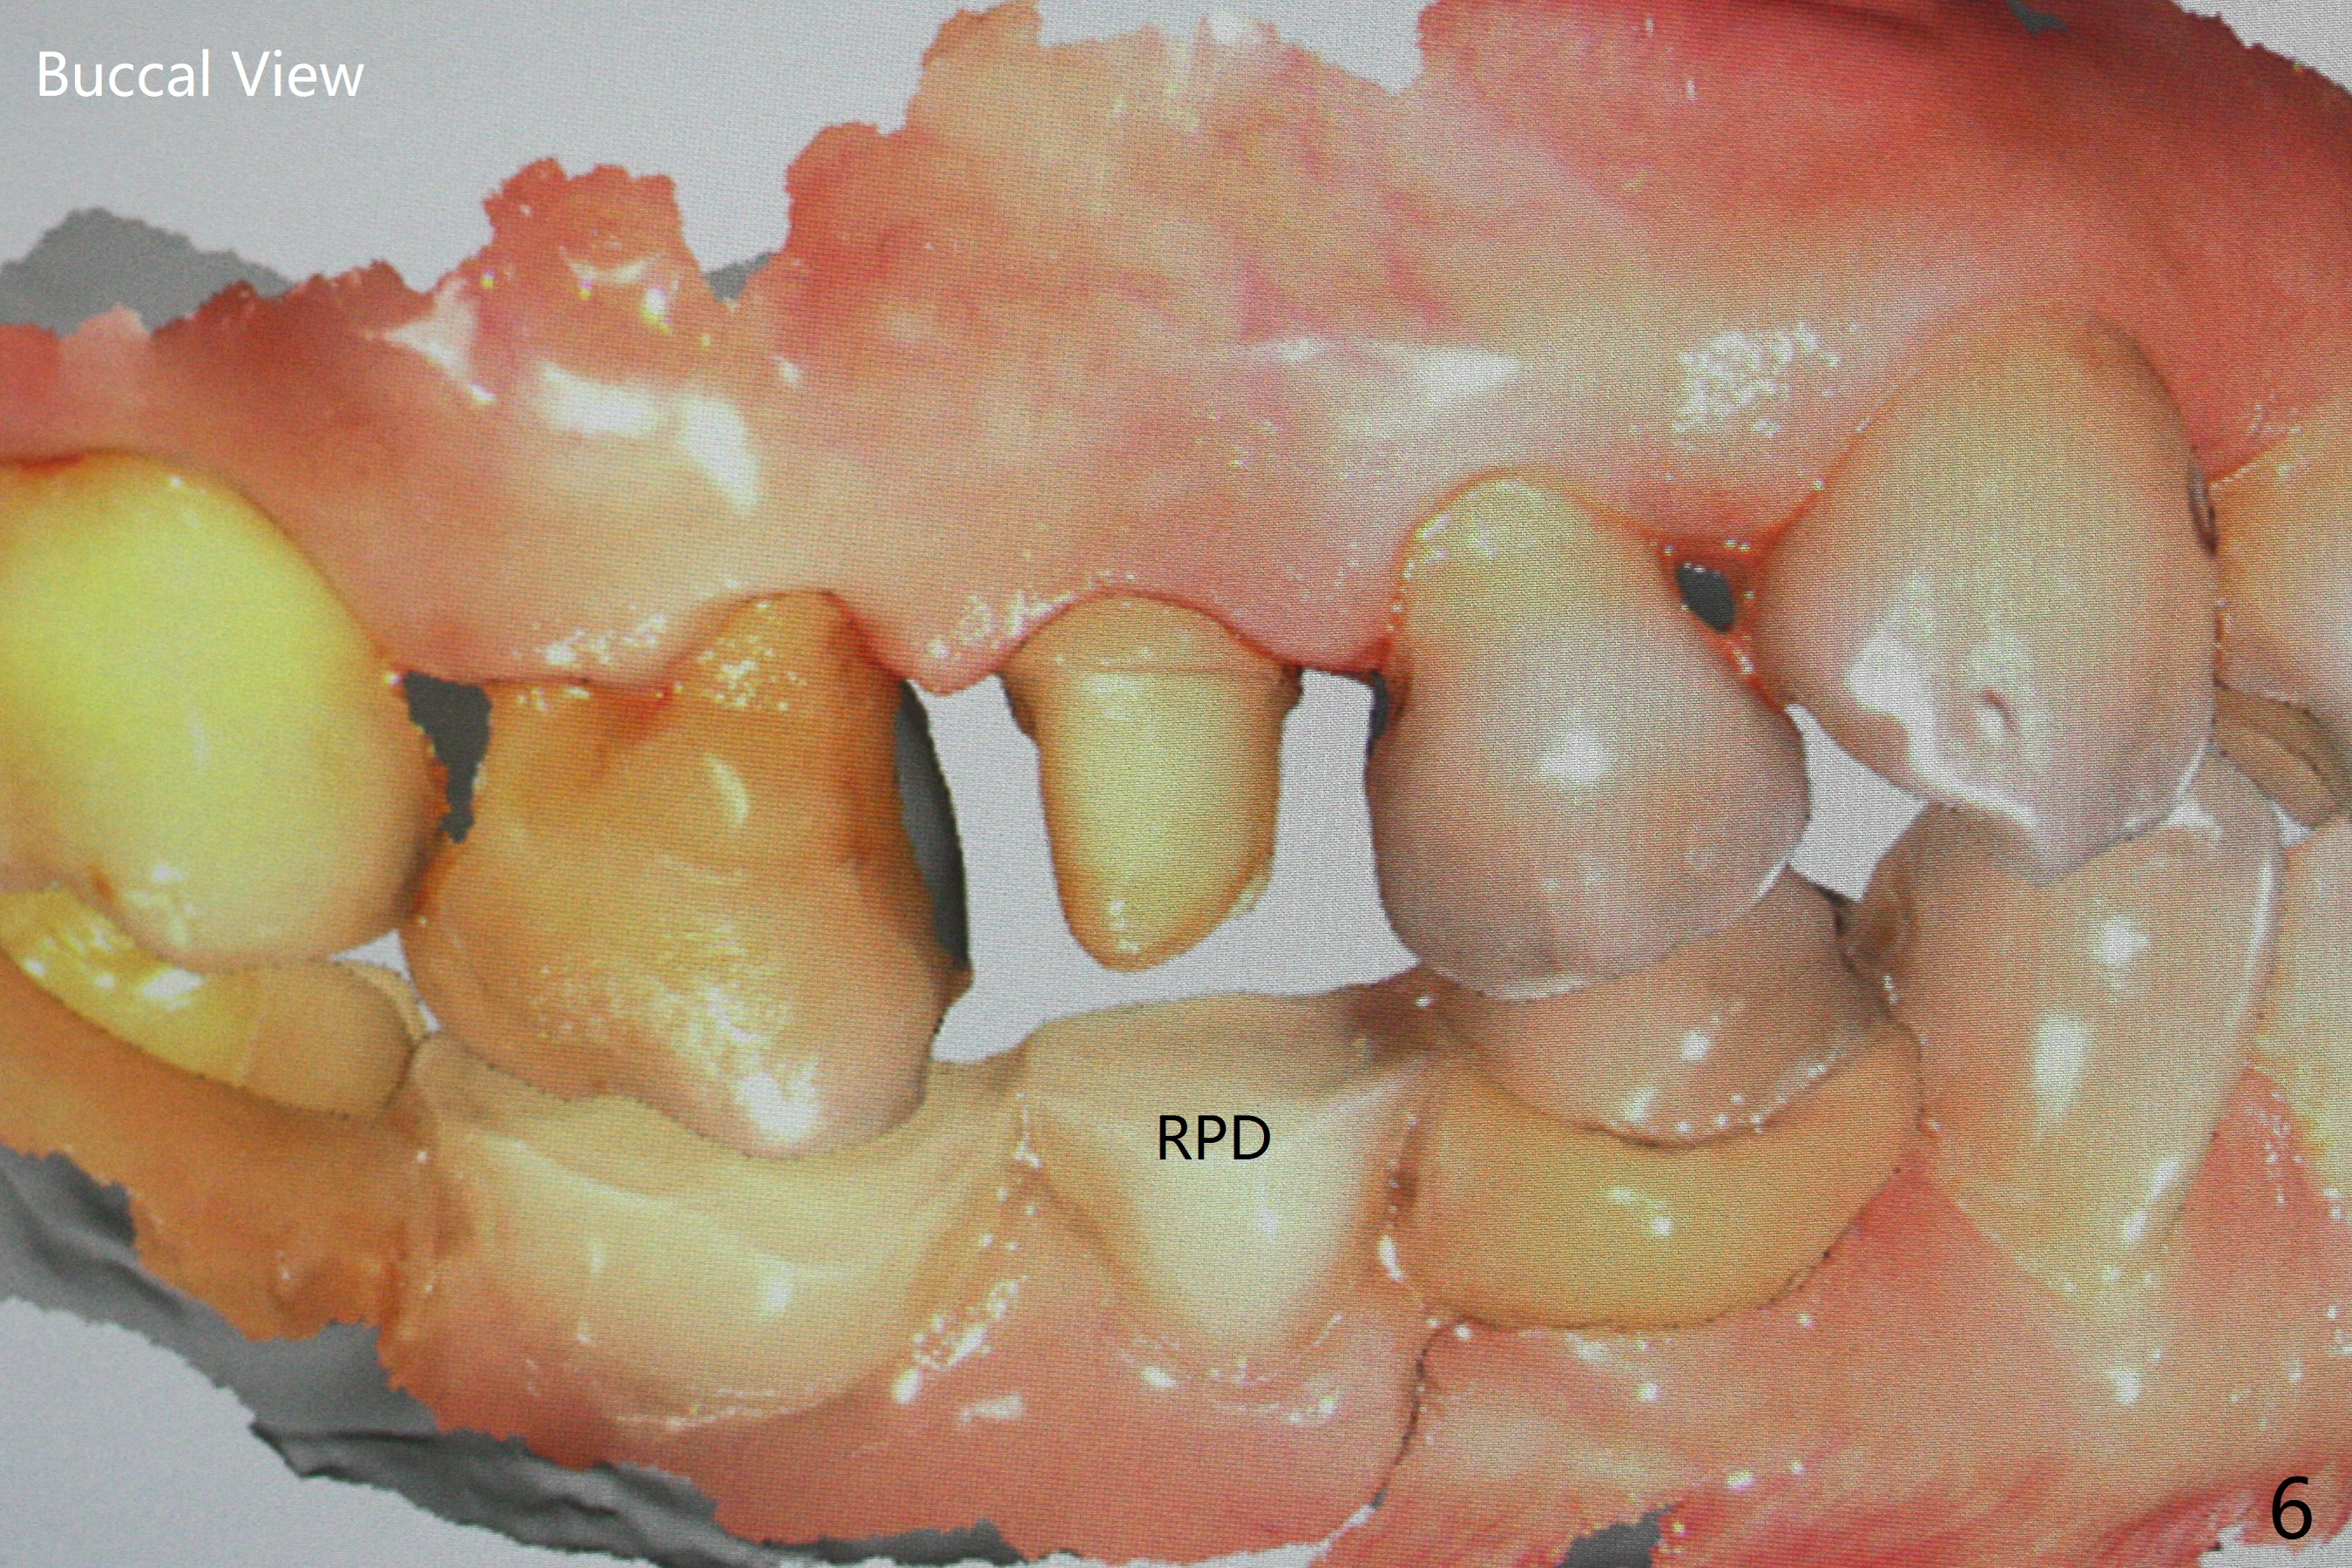

52岁女去年在外州开始4号牙根管治疗(图一),由于新冠病毒和搬家而拖延治疗,现在要求完成根管治疗(图二,三),B: 颊侧(主牙胶尖:20/.04);L: 舌侧(旋转锉:20/.04)。Shining口扫(图四(咬合面观),五(舌侧观),六(颊侧观;对合:局部托牙 (RPD)))。为了保险起见,要求实验室制作两个牙冠:取模,口扫。帮助实验室建立完善数字化系统,从而帮助临床工作。备牙边缘清晰(图八)。牙冠边缘与数字模型(图九)和牙齿吻合,天衣无缝。

Root canal therapy (RCT) was initiated for the tooth #4 of a 52-year-old lady out of state approximately 8 months earlier (Fig.1). The patient requested finishing the treatment and permanent crown fabrication. The buccal (Fig.2 B (master cone 20/.04)) and lingual (L (rotary file 20/.04))) canals fuse near the apex. RCT was done with insertion of 20/.04 and 20/.06 master cones in the buccal and lingual canals, respectively, followed by composite build-up (Fig.3). With basically shoulder margin (not feather margin, chamfer margin ok), it is easy to scan (Fig.4-6 (RPD: removable partial denture)). Return to Oral Scanner Xin Wei, DDS, PhD, MS 1st edition 06/05/2021, last revision 06/25/2021